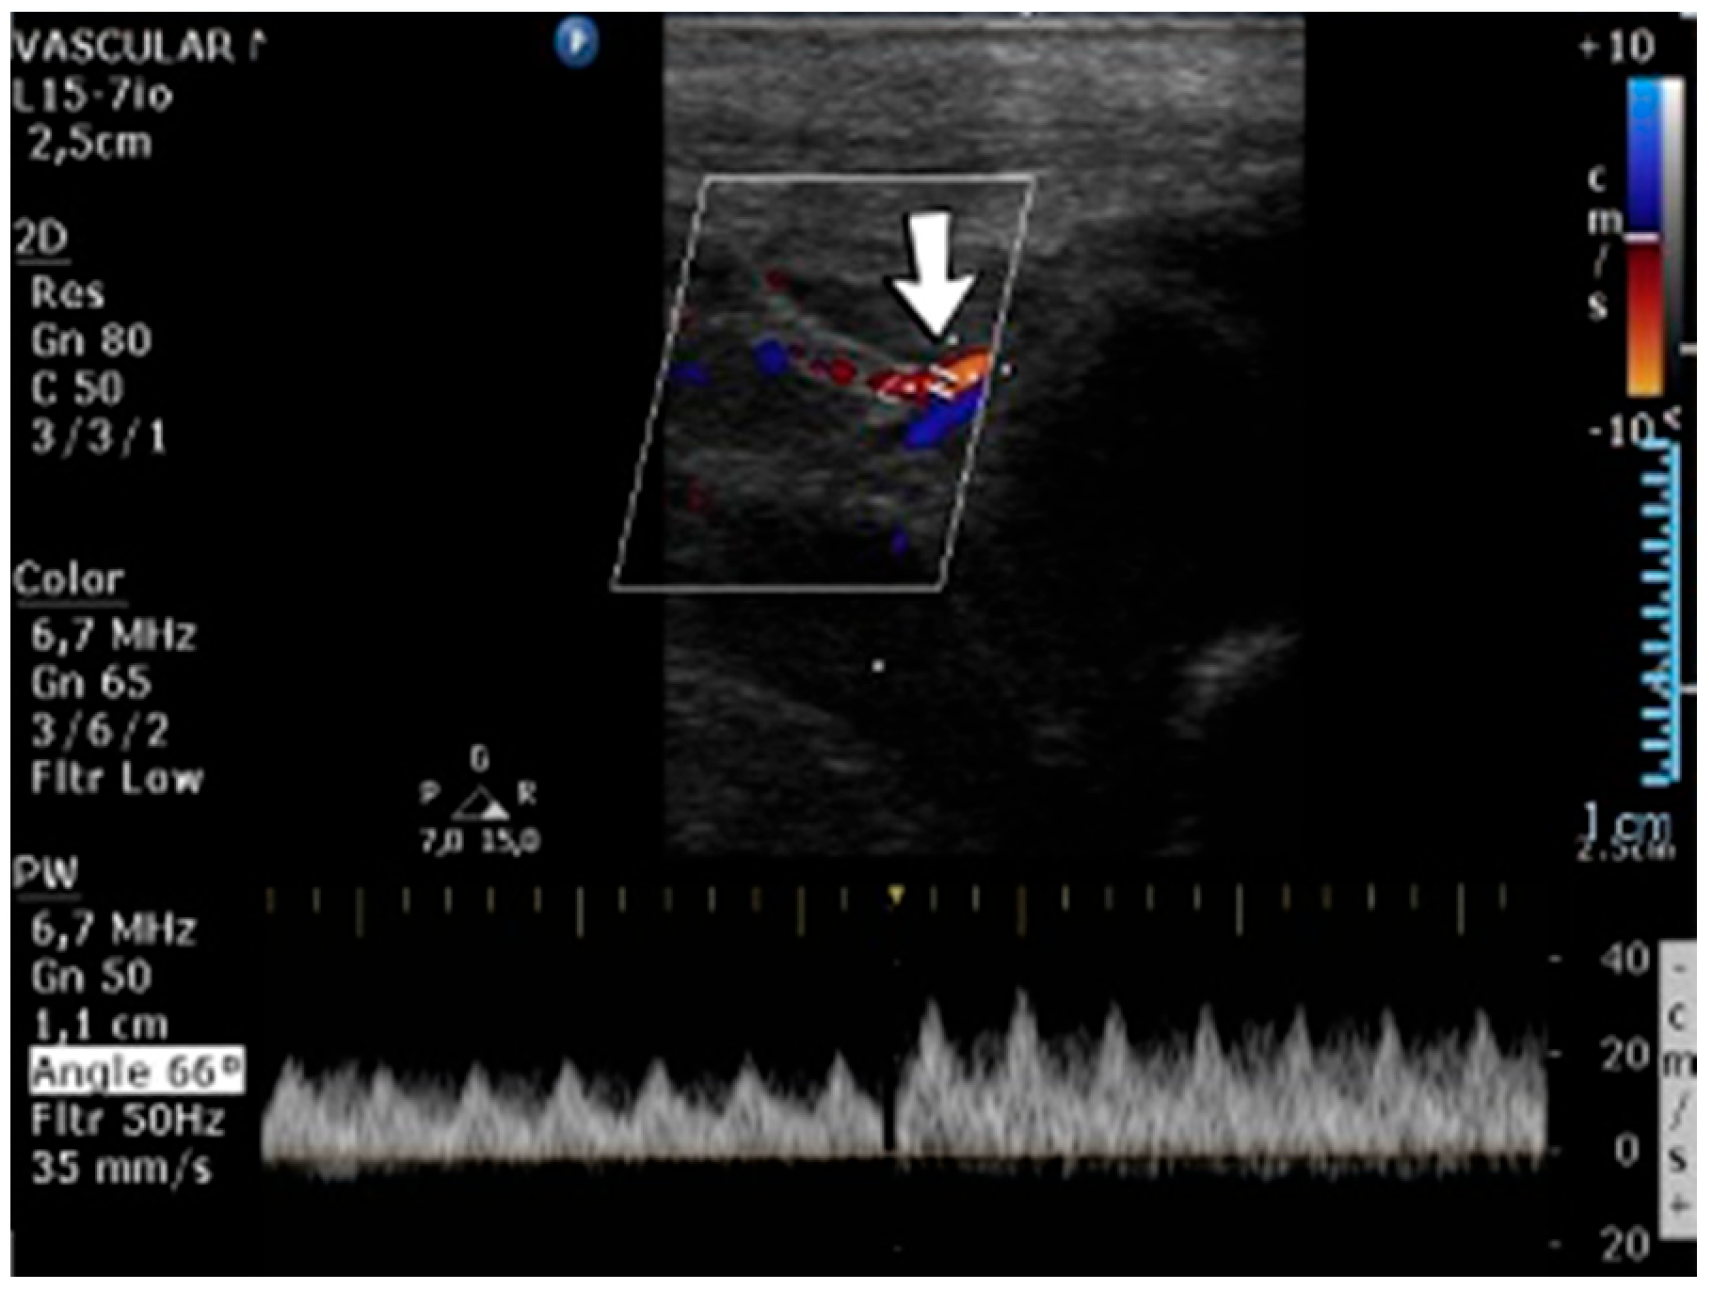

4.34. Case No. 34—Postnatal Thrombosis of the Right Axillary Artery

A 10-day-old female neonate (36 weeks, 2.37 kg), known before birth with Dandy–Walker Syndrome, presented with hydrocephalus and severe coarctation of the aorta. Two central arterial lines were placed—in the right brachial and the left femoral arteries—and the aortic defect was corrected. One day later, hematoma of the right arm and ecchymosis near the insertion site of the brachial arterial catheter were noticed. Vascular ultrasound could not reveal any blood flow on the axillary or the proximal brachial arteries, leading to the removal of the central arterial catheter (Figure 14). Continuous heparin infusion was initiated, followed by treatment with enoxaparin. Later, blood flow was reestablished on both axillary and brachial arteries.

Figure 14.

No blood flow on the axillary or the proximal brachial arteries on vascular ultrasound.

Genetic testing confirmed inherited thrombophilia, with a positive MTHFR C677T homozygous gene mutation and Antithrombin, Protein S, and Protein C deficiencies. Normal PAI-1 levels were detected. There was a positive family history of maternal thrombophilia (MTHFR A1298C, MTHFR C677T, PAI-1 4G/5G promoter, and Factor XIII (Val34Leu) heterozygous gene mutations and Protein S deficiency), treated with enoxaparin and acetylsalicylic acid during pregnancy. There were no maternal miscarriages.